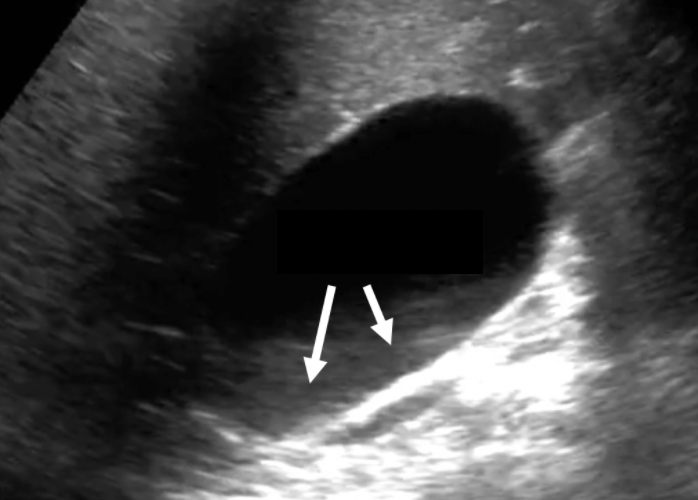

Name this artifact.

What is the cause of the artifact? How would you (try to) fix it?

Edge shadowing artifact: Refractive artifact that occurs at the edge of a large curved boundary with a different speed of sound than that of the surrounding tissues

FIX: spatial compounding, change angle of insonation